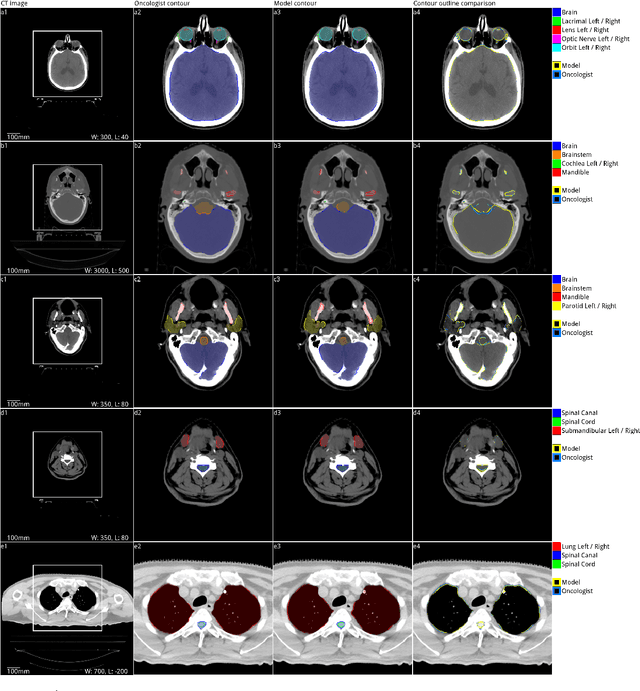

Abstract:Over half a million individuals are diagnosed with head and neck cancer each year worldwide. Radiotherapy is an important curative treatment for this disease, but it requires manually intensive delineation of radiosensitive organs at risk (OARs). This planning process can delay treatment commencement. While auto-segmentation algorithms offer a potentially time-saving solution, the challenges in defining, quantifying and achieving expert performance remain. Adopting a deep learning approach, we demonstrate a 3D U-Net architecture that achieves performance similar to experts in delineating a wide range of head and neck OARs. The model was trained on a dataset of 663 deidentified computed tomography (CT) scans acquired in routine clinical practice and segmented according to consensus OAR definitions. We demonstrate its generalisability through application to an independent test set of 24 CT scans available from The Cancer Imaging Archive collected at multiple international sites previously unseen to the model, each segmented by two independent experts and consisting of 21 OARs commonly segmented in clinical practice. With appropriate validation studies and regulatory approvals, this system could improve the effectiveness of radiotherapy pathways.